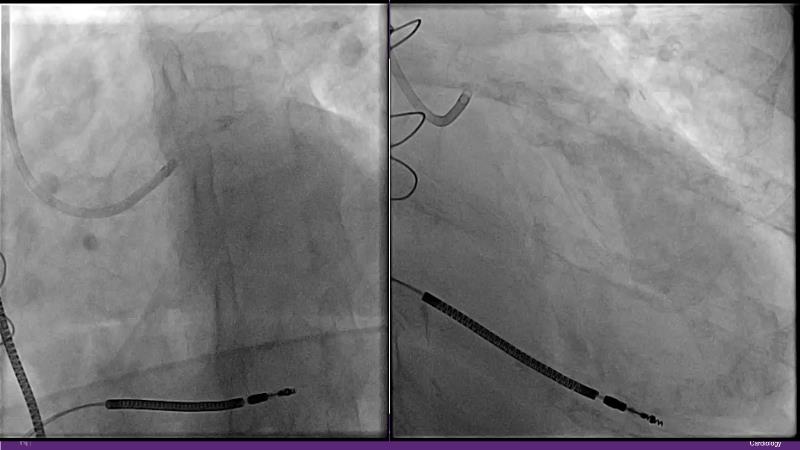

Cracking calcium: best practices to integrate intravascular lithotripsy into your calcium management algorithm

With this session, keep up to date on the evidence, trials and outcome data for intravascular lithotripsy in severely calcified lesions. Learn how to use this technique in real-world patients and understand its role in the treatment algorithm for severely calcified coronary lesions.

- To learn how to use intravascular lithotripsy in real-world patients with severely calcified coronary lesions